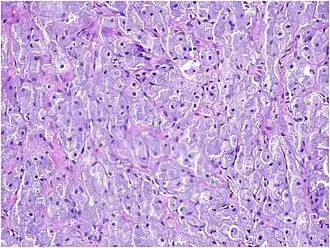

Histopathologically, congenital epulis is usually characterized by the presence of big, rounded cells that fill the mucosa's lamina propria and have round to oval nuclei and an abundance of eosinophilic cytoplasm.[10] A thin layer of connective tissue separated the surface layer of cells from the growing new cells. Numerous histological traits, such as a fibrous and granulomatous appearance, have been reported in recent research.[10]

A low-power microscopic image reveals stratified squamous epithelium with a subepithelial proliferation of large polygonal cells arranged in nests and dense sheet [7]

A medium-power microscopic view displays nests and sheets of large polygonal cells with abundant granular eosinophilic cytoplasm and a centrally located nucleus [7]

A high-power microscopic view reveals variably sized blood vessels scattered throughout certain areas of the lesion [7]

Microscopically, congenital epulis is composed of:

• Sheets of proliferating polygonal to round cells with overlying thin squamous, eosinophilic, granular cytoplasm[12][13]

• Centrally located, round nuclei [7]

These histopathological features are essential in distinguishing congenital epulis from other gingival and soft tissue neoplasms.